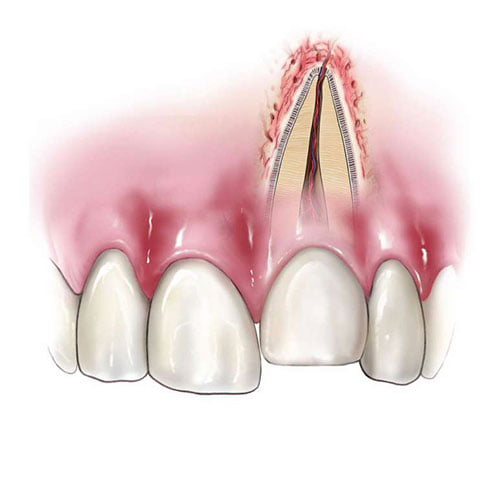

Czym jest elektrokoagulacja? Elektrokoagulacja to zabieg polegający na kontrolowanym wykorzystaniu prądu elektrycznego w celu zamknięcia naczyń krwionośnych oraz usunięcia zmienionych tkanek. W stomatologii metoda ta znajduje zastosowanie przede wszystkim w chirurgii i periodontologii. Stomatolog w nowoczesnej klinika stomatologiczna Kraków wykorzystuje…